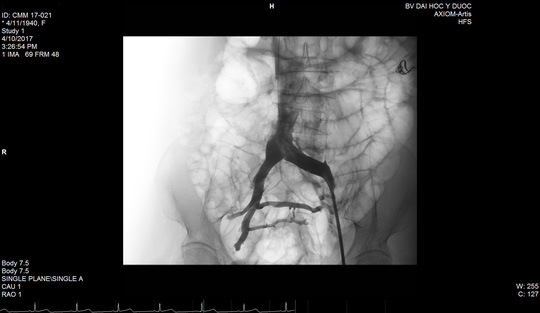

Và mạch máu đã lưu thông lại nhiều sau khi được đặt stent.